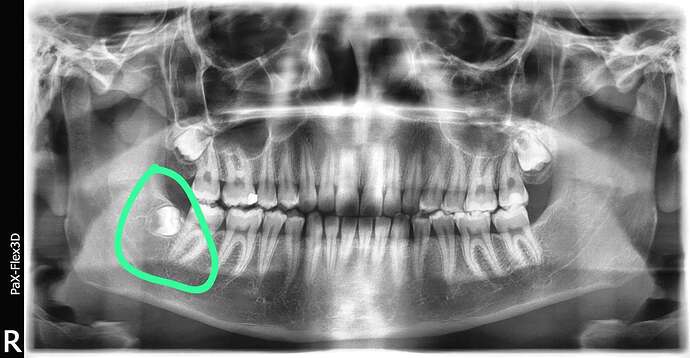

Ik ga twee keer per jaar naar een hele fijne mondhygieniste waar ook een tandarts in dezelfde praktijk zit. Om de 2 jaar ofzo schuif ik even door naar de stoel van de tandarts (5 minuten) voor een hele snelle check. Er is nooit iets aan de hand, nog nooit een gaatje gehad en heb nooit ergens last van. Het enige waar ze al jaren over beginnen zijn mijn verstandskiezen. Die moeten er (preventief) uit, want, “dat kun je nooit goed schoonhouden”. De verstandskiezen zijn door, onderin liggen ze redelijk ‘plat’ en bovenin zijn normaal. Ik heb al eens een uitgebreide foto van m’n verstandskiezen laten maken waar ze tot de conclusie kwamen dat een kaakchirurg ze er beter uit kon halen. Ik raakte toen zwanger en vond dat een mooi excuus om het nog even voor me uit te schuiven. Ik zie er enorm tegenop om ze te laten trekken (zeker ook omdat het in twee keer moet) en zie zelf de urgentie ook niet echt, waardoor ik het maar voor me uit blijf schuiven.

tanden foto